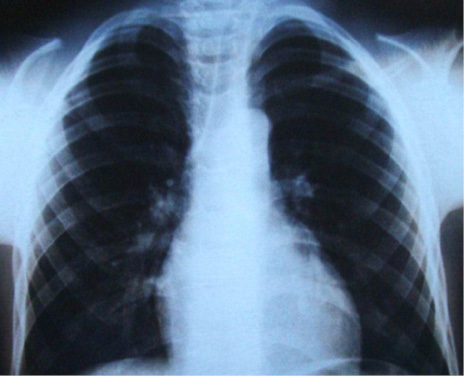

En el estudio imagenológico se observó en la radiografía de tórax, hipoplasia clavicular bilateral y tórax en forma de campana (Figura 2), en la radiografía panorámica se mostró la presencia de once dientes supernumerarios en el maxilar y nueve en la mandíbula (Figura 3), en la radiografía lateral cráneo se observó presencia de huesos wormianos landoideos (Figura 4); en la radiografía carpal se observó longitud simétrica de las falanges y sin alteraciones (Figura 5), de acuerdo con los hallazgos encontrados en el examen físico y la evaluación radiológica, se realizó la impresión diagnóstica de displasia cleidocraneal.